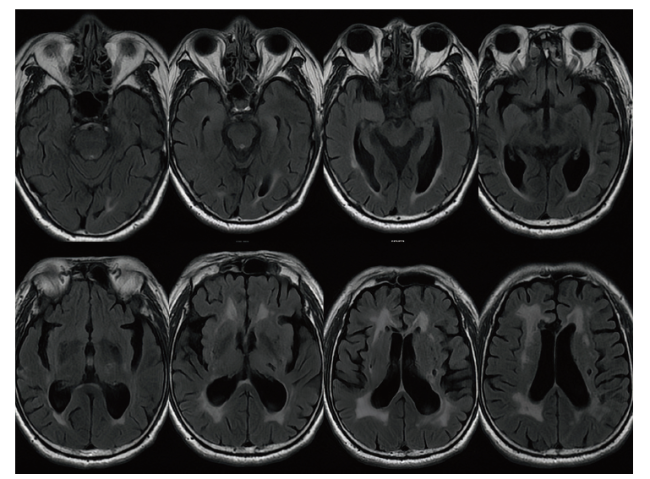

血清及脑脊液LGI1抗体均(+)。脑脊液检查:压力180 mmH2O,氯124.8 mno1/L,葡萄糖3.8 mmol/L,电解质未见异常。颅脑MRI:脑内多发梗死灶及软化灶,部分软化灶周围伴胶质增生(图1)。

图1 一例复发性且MRI阴性的LGI1抗体相关脑炎患者MRI检查

注:T2序列未见异常信号,仅有部分梗死灶及软化灶。

本病的MRI典型表现为单或双侧海马、颞叶的T2及液体衰减反转恢复序列(FLAIR)呈现高信号,部分患者的病灶累及基底节、岛叶及丘脑,亦有部分患者无MRI异常,PET-CT检查则多发现其颞叶内侧或基底节存在异常代谢[14]。本病另一个重要的诊断依据是血清及脑脊液特异性LGI1抗体(+),本例患者MRI未出现异常信号,脑脊液LGI1抗体(+)可作为明确诊断的依据,患者家属暂不同意行PET-CT检查。